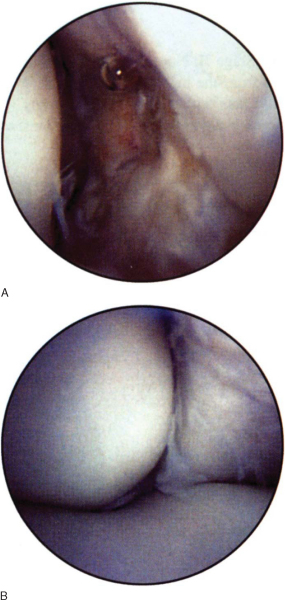

Through the anteromedial portal (

Fig. 31-9

), established under direct vision by initial placement of an 18-gauge needle, the radial head and the radiocapitellar articulation can be identified. Supination and pronation of the forearm allow viewing of 75% of the surface of the radial head. The annular ligament can be noted crossing the radial neck, and the radial fossa can be evaluated with proximal viewing of the scope. The attachment of the capsule to the humerus can be seen superiorly. The scope can then be advanced to examine the lateral gutter, the undersurface of the capsule, and the origin of the extensor muscles to the lateral epicondyle. The articulations of the radius, ulna, and distal humerus can be viewed by placing the scope between the trochlear and capitellar ridges up to the medial border of the radial head.

Figure 31-9 (From Phillips BB. Arthroscopy of upper extremity. In Canale ST, ed. Campbell’s Operative Orthopaedics, 10th ed. St. Louis, Mosby, 2003.) |